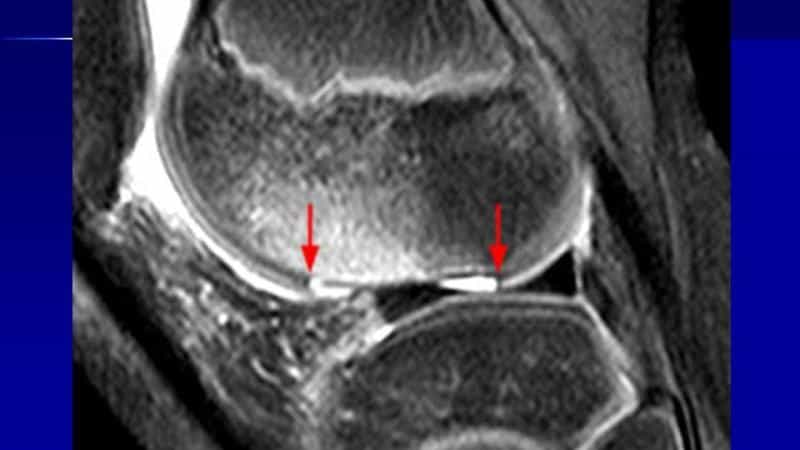

Остеоартроз. Дефект суставного хреща